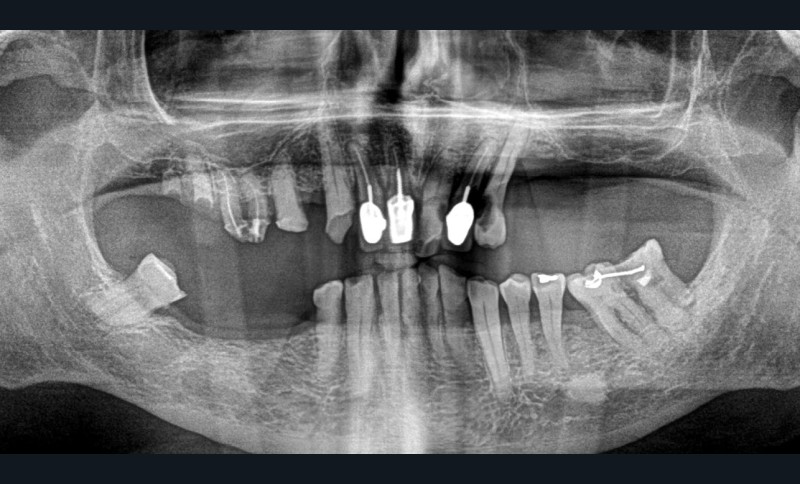

Un patient de 84 ans, en bon état de santé générale, consulte pour la perte de trois couronnes solidarisées métalliques 17, 16 et 15 qui permettaient la rétention d’une PAP à châssis métallique (fig. 1 à 5).

L’examen clinique permet de mettre en exergue, au maxillaire :

– 17, 16 sont à l’état de racines, 15 est déjà préparée et ne présente aucune symptomatologie pulpaire ;

– 13 est intacte ;

– 12 est couronnée et présente une mobilité importante et un épaississement ligamentaire ;

– 11 est couronnée ;

– carie radiculaire importante à la 21 ;

– 22 est couronnée et présente également une carie radiculaire ;

– 13 est très cariée et présente une alvéolyse dépassant le tiers apical de la racine.

À la mandibule, nous notons que :

– les dents 45, 46, et 47 sont absentes ;

– la dent 37 est liée à 36 par un jonc retenu dans un composite et présente une image apicale et une alvéolyse distale dépassant le tiers de la racine. L’édentement n’a jamais été compensé.